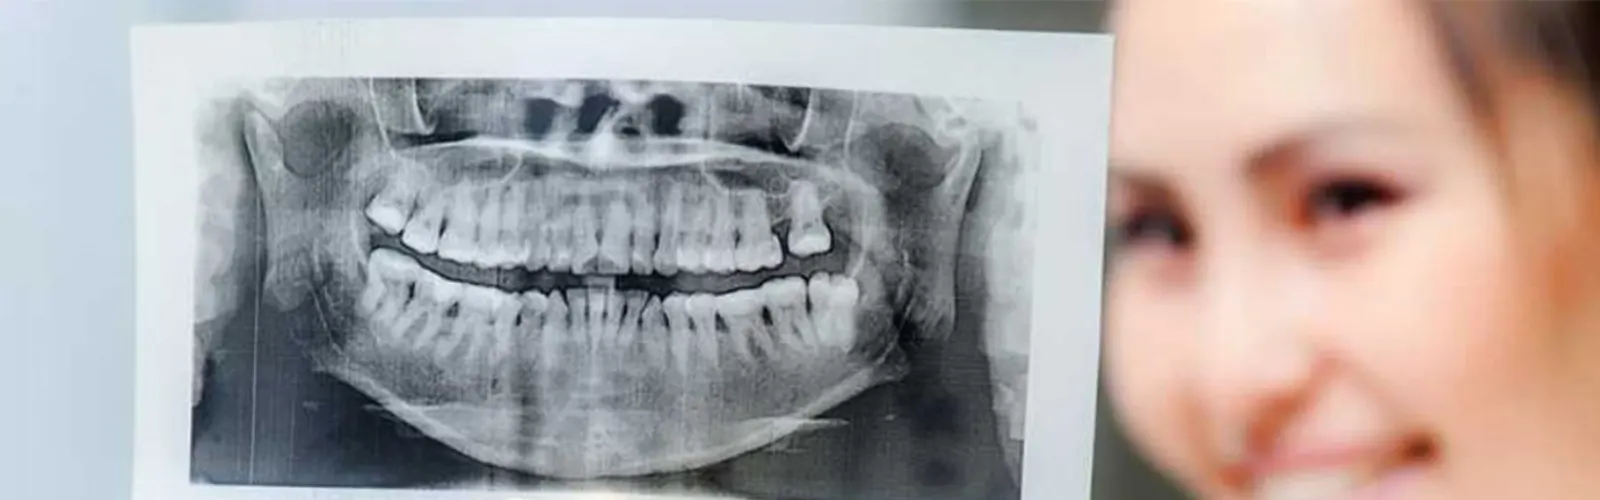

An OPG (orthopantomogram) scan is a type of dental X-ray that provides a panoramic view of the teeth, jaws, and surrounding structures. It is used to diagnose and plan treatment for a variety of dental conditions, including:

OPG scans can provide a detailed image of the jawbone and help determine whether there is enough bone to support dental implants.